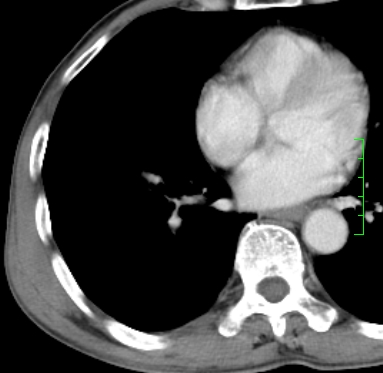

m,73y。膝关节疼痛伴双下肢水肿。入院常规胸片发现结节灶。增强为静脉期。

指套征,强化明显,近侧肺组织局限性肺气肿,考虑支气管类癌,慢支、肺气肿、双上陈旧性tb、冠脉钙化。

1)考虑右肺下叶周围型肺癌。2)右肺上叶及左肺感染性病变(结核可能)。3)肺气肿。4)冠状动脉钙化。